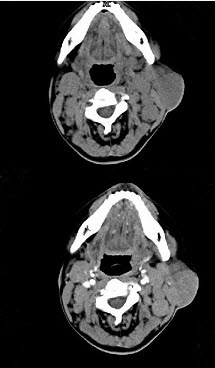

女,25岁、发现双侧颈部肿块近10年,CT如图,最可能的诊断为()。

A、巨淋巴结增生症

B、淋巴瘤

C、转移癌

D、淋巴结结核

E、淋巴结炎

A